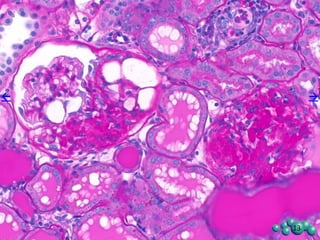

Pathological Evaluation of Kidney

• Glomerulopathy: Changes in the renal glomeruli consisted of one or more of the following:

positively with the PAS stain and to a lesser extent with the Trichrome stain.

• Tubular dilation/degeneration: This change was mainly in the cortex and consisted of irregularly

present, frequently in association with the interstitial inflammatory response, but not restrictively so.

• Protein casts: Individual tubules contained acellular, uniformly staining eosinophilic material

• Inflammation: The inflammatory process consisted of focal collections of lymphocytes and

and individual blood vessels, and in association with the renal pelvic epithelium.

Kidney Histopathology of the ZDSD Rat

Glomerulopathy Tubular dilation Protein casts Inflammation